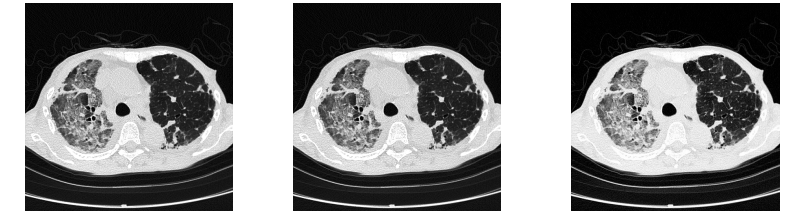

Poniżej zestawiono oceniane obrazy dla porównania.

Rys. 14 Przykładowe obrazy CT (Hybrid Gamma PXL po lewej, GSDF w środku, 2.2 po prawej)